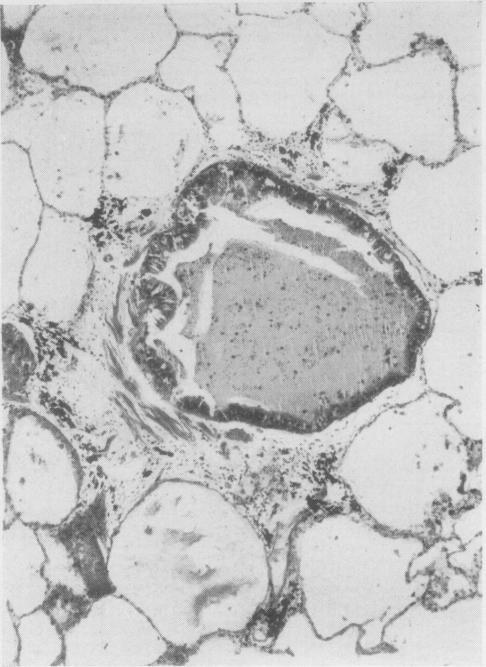

ESTERLY J R, HEARD B E

Thorax. 1965 Jul;20(4):309-16. doi: 10.1136/thx.20.4.309.